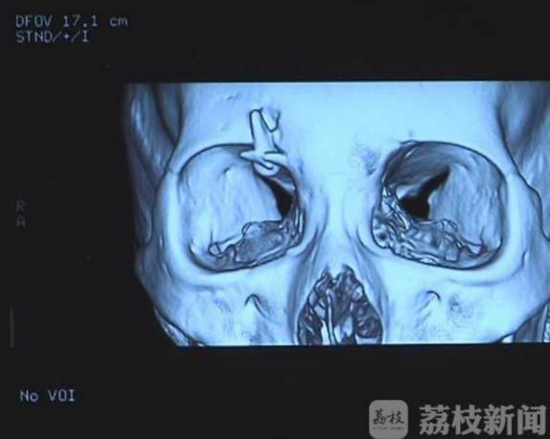

江苏省中医院神经外科医生傅传经说,从片子来看,在婷婷右侧眼眶的上缘,能看到一个类似于牙齿形状的异物,结合对方患者的门牙,高度怀疑异物就是个牙齿。由于牙齿釉质比骨头密度还要高,牙齿前面也是比较锐利的,如果相撞的时候,正好是锐口对骨头,这个瞬间牙齿是能够将骨头戳穿,卡进入骨头里的。婷婷的母亲说,电动车相撞时,对方确实缺损了三颗门牙,当时也没有找到门牙的去处。今天中午,婷婷在江苏省中医院神经外科接受了手术,在避免损伤周围的视觉神经的前提下,医生将卡在眉骨上的牙齿取下来。